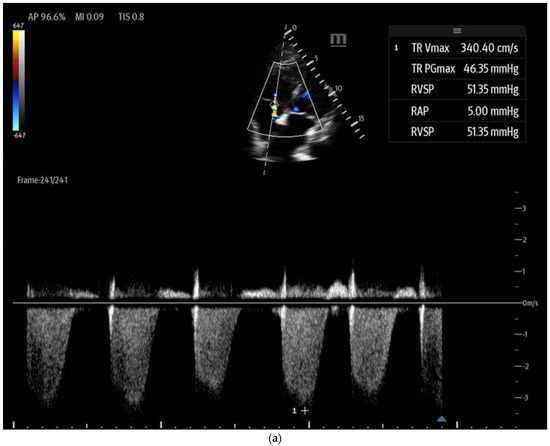

- Point-of-care ultrasound markers of RV afterload:

- Tricuspid regurgitation (TR) jet velocity: Pulmonary artery (PA) pressures can be estimated using TR jet peak velocity (Figure 8a). The evidence suggests that in the right clinical context, a TR jet velocity greater than 2.8 m/s is an independent predictor of pulmonary hypertension, while a velocity > 3.4 m/s strongly indicates this condition [35,43,44]. However, this method has limitations as TR jet velocity may underestimate PA pressures in cases of severe TR and is unreliable when TR is insufficient for evaluation [43]. Additionally, this technique cannot differentiate pulmonary hypertension from other causes of RV outflow obstruction, such as pulmonary or RVOT stenosis [44].